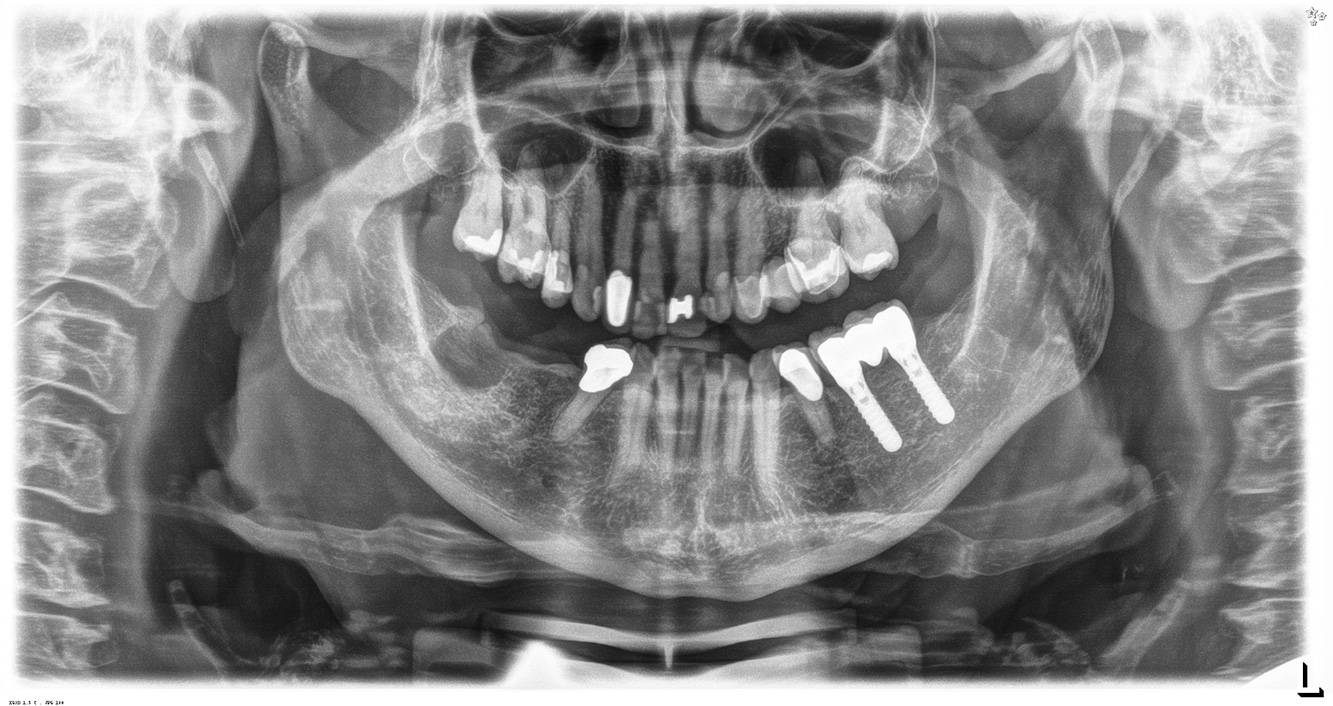

Die 68-jährige Patientin hat keine zahnmedizinisch relevanten allgemeingesundheitlichen Vorerkrankungen oder Medikation, auch aus dem Lebensstil ergibt sich kein besonderes Risiko. Die Patientin hat zwei Implantate (3. Quadrant, seit fünf Jahren) sowie eine parodontale Vorerkrankung (Parodontitis Stadium IV, Grad B) mit Zahnverlust. Derzeit zeigen sich stabile parodontale Verhältnisse, jedoch erhöht Parodontitis maßgeblich die biologischen Komplikationen bei Implantationen und es droht der Implantatverlust (21).

Aufgrund der Implantatsituation mit parodontaler Vorerkrankung hat die Patientin ein Entstehungsrisiko für eine Periimplantitis – empfohlen wird eine Wiedervorstellung im Intervall von drei bis vier Monaten.